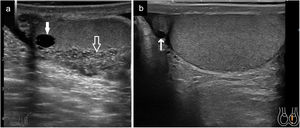

Ecográficamente se caracteriza por aumento de flujo en el Doppler color. Suele ser unilateral. El epidídimo puede estar aumentado de tamaño y ser heterogéneo (vídeo 3). Puede existir hidrocele reactivo y engrosamiento de las cubiertas escrotales. Habitualmente comienza afectando a la cola del epidídimo y se extiende al cuerpo y a la cabeza y si la infección progresa también al testículo (orquioepididimitis). En la orquitis el testículo puede presentar una ecogenicidad heterogénea y hay un aumento del flujo en el Doppler-color en el testículo afecto, al compararlo con el contralateral1,14,28,29 (Fig. 7).

a) Epididimitis con engrosamiento e hipoecogenicidad del epidídimo (señalado con flechas y medido su grosor entre cruces); b) Orquitis avanzada con zonas de marcada hipoecogenicidad del parénquima testicular y área periférica abscesificada con captación Doppler; c) Evolución de «b» una semana después con área abscesificada en polo inferior testicular con hidrocele tabicado secundario (señalado con flechas).